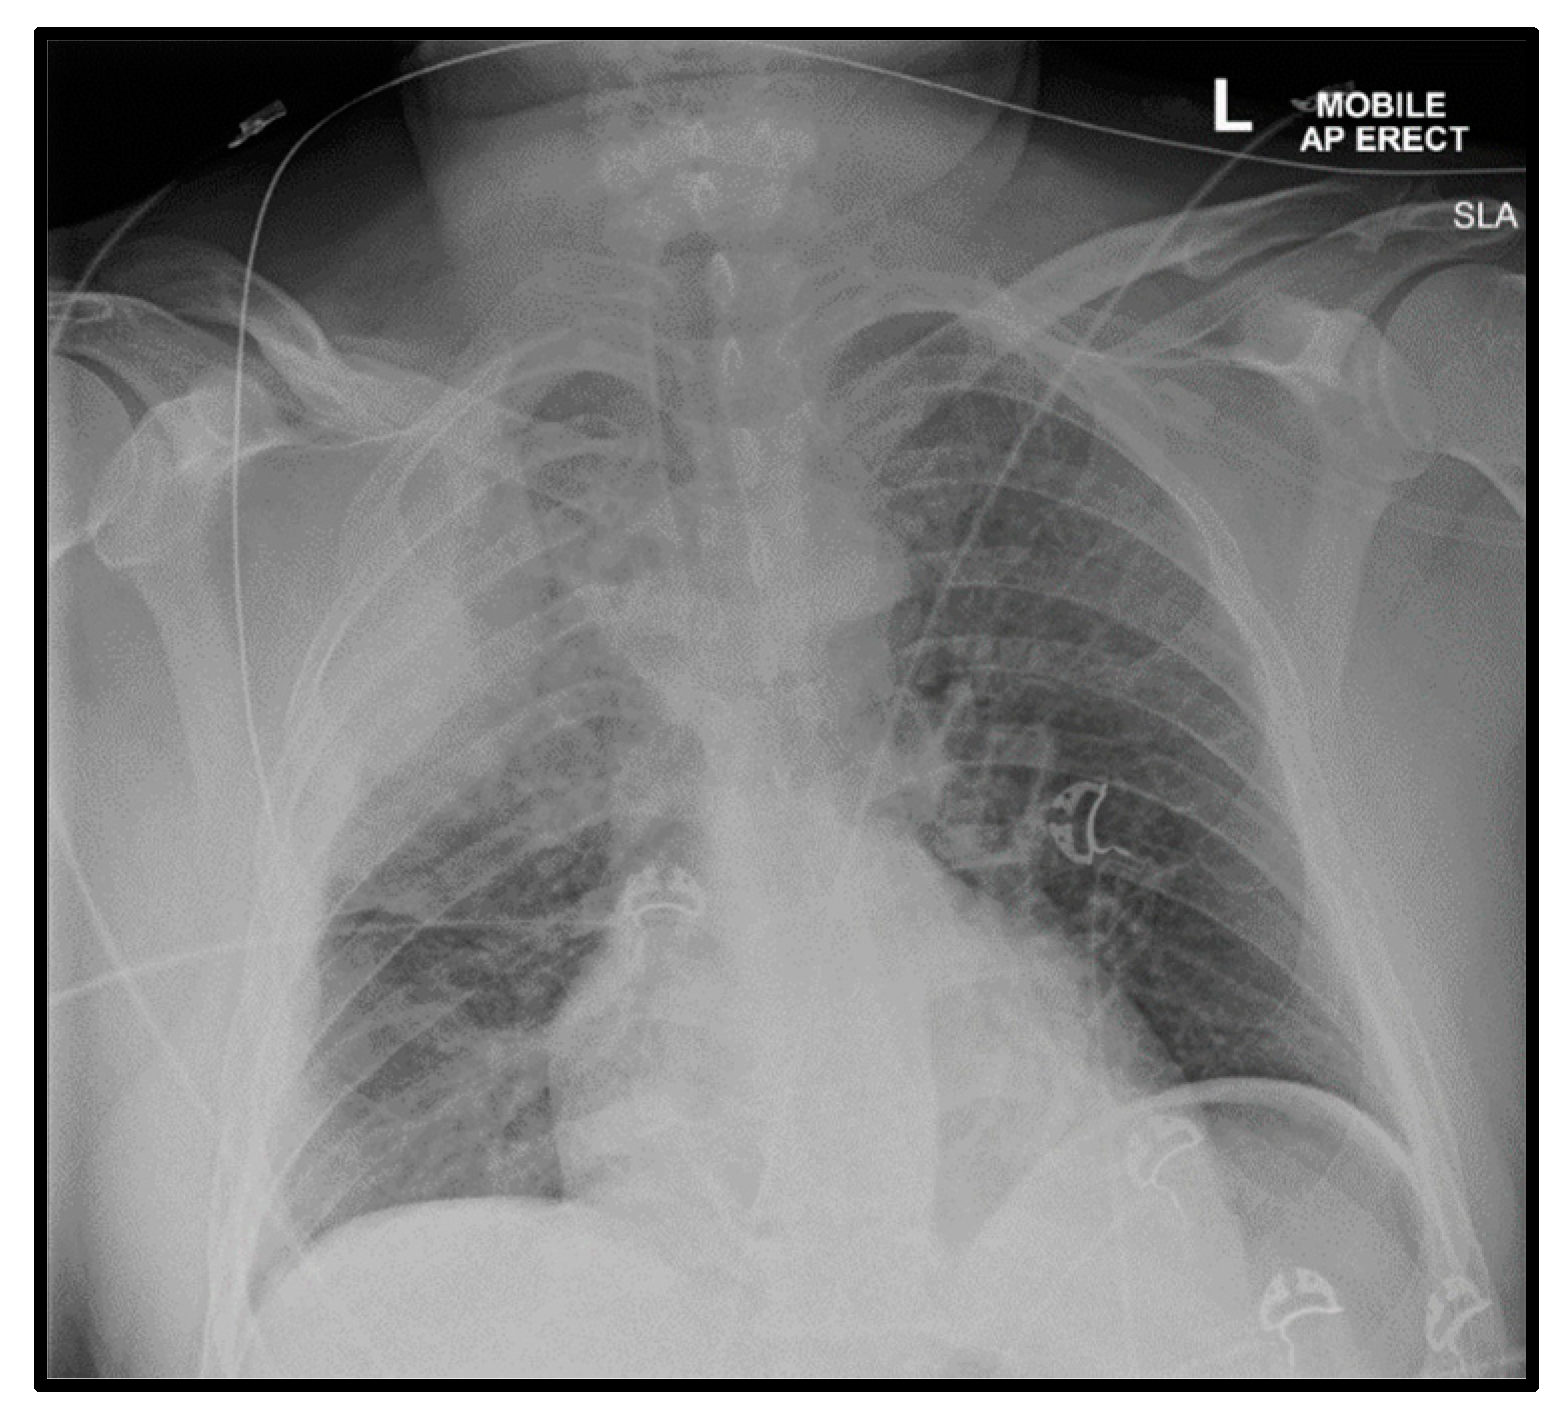

The intra-procedural description and images are provided in Figure 4. A 14-French Pigtail intercostal catheter was inserted post-procedure which drained an approximate amount of 700 mL of blood in an hour. The intercostal catheter was left in situ at a draining pressure of negative 20 mmHg. Repeat bloods showed a further significant drop in hemoglobin, from 135 g/dL to 95 g/dL, to 90 g/dL, to 81 g/dL, down to 78 g/dL, with a raised lactate of 3.9 mmol/L. A repeat CT angiogram was carried out to evaluate for any causes of active bleeding; the images can be found in Figure 5. As a result of no significant findings on the CT angiogram to account for the falling hemoglobin, an explorative thoracotomy was agreed upon. An extrapleural hematoma of approximately 2 L of blood was found in the extrapleural space. No active bleeding source was found. There was a collapsed right lung sparing the apical and anterior segments of the upper zone. The right lung fully expanded post-drainage of the blood in the extrapleural space. He remained intubated for 5 days post-explorative thoracotomy on a noradrenaline infusion. Despite developing ventilator-associated pneumonia and being severely deconditioned secondary to these events, he recovered well over the course of a week and was discharged back to the regional hospital for further rehabilitation. CXR prior to discharge is shown in Figure 6. A concise timeline of the key sequences of events at each site is shown in Figure 7.

Figure 6. Discharge CXR—nasogastric tube in situ. Persistent bands of atelectasis in right lower zone.